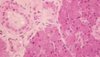

Name the following tissue and category.

Glandular epithelium in the intestinal mucosa

Name the following Glandular epihelia.

Parotid gland – serous gland